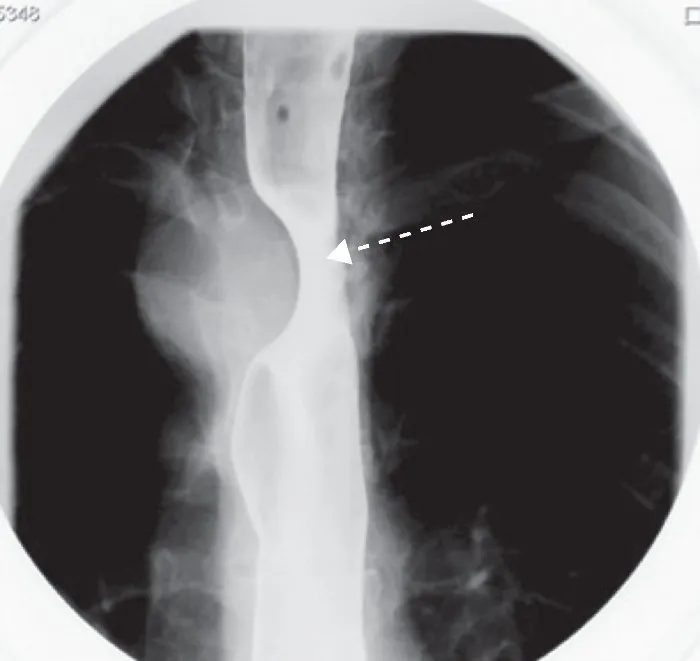

Esophageal Dysphagia is investigating insidious onset of rule by upper endoscopy; however subtle rings and networks can not visualize if it is given a barium swallow solid using a bolus. Barium swallow is also an initial test in esophageal dysphagia although biopsies and endoscopy require esophageal dilation. Esophageal manometry esophageal motor disorders can specify when other tests are normal or suggest a motility disorder.

Esofagografia with dye versus endoscopy provides limited information on esophageal motility. Many clinicians perform direct endoscopy when suspected mechanical damage. Dysphagia in patients with esophageal motility disorders due to a possible, be performed first Esophagoscopy barium.